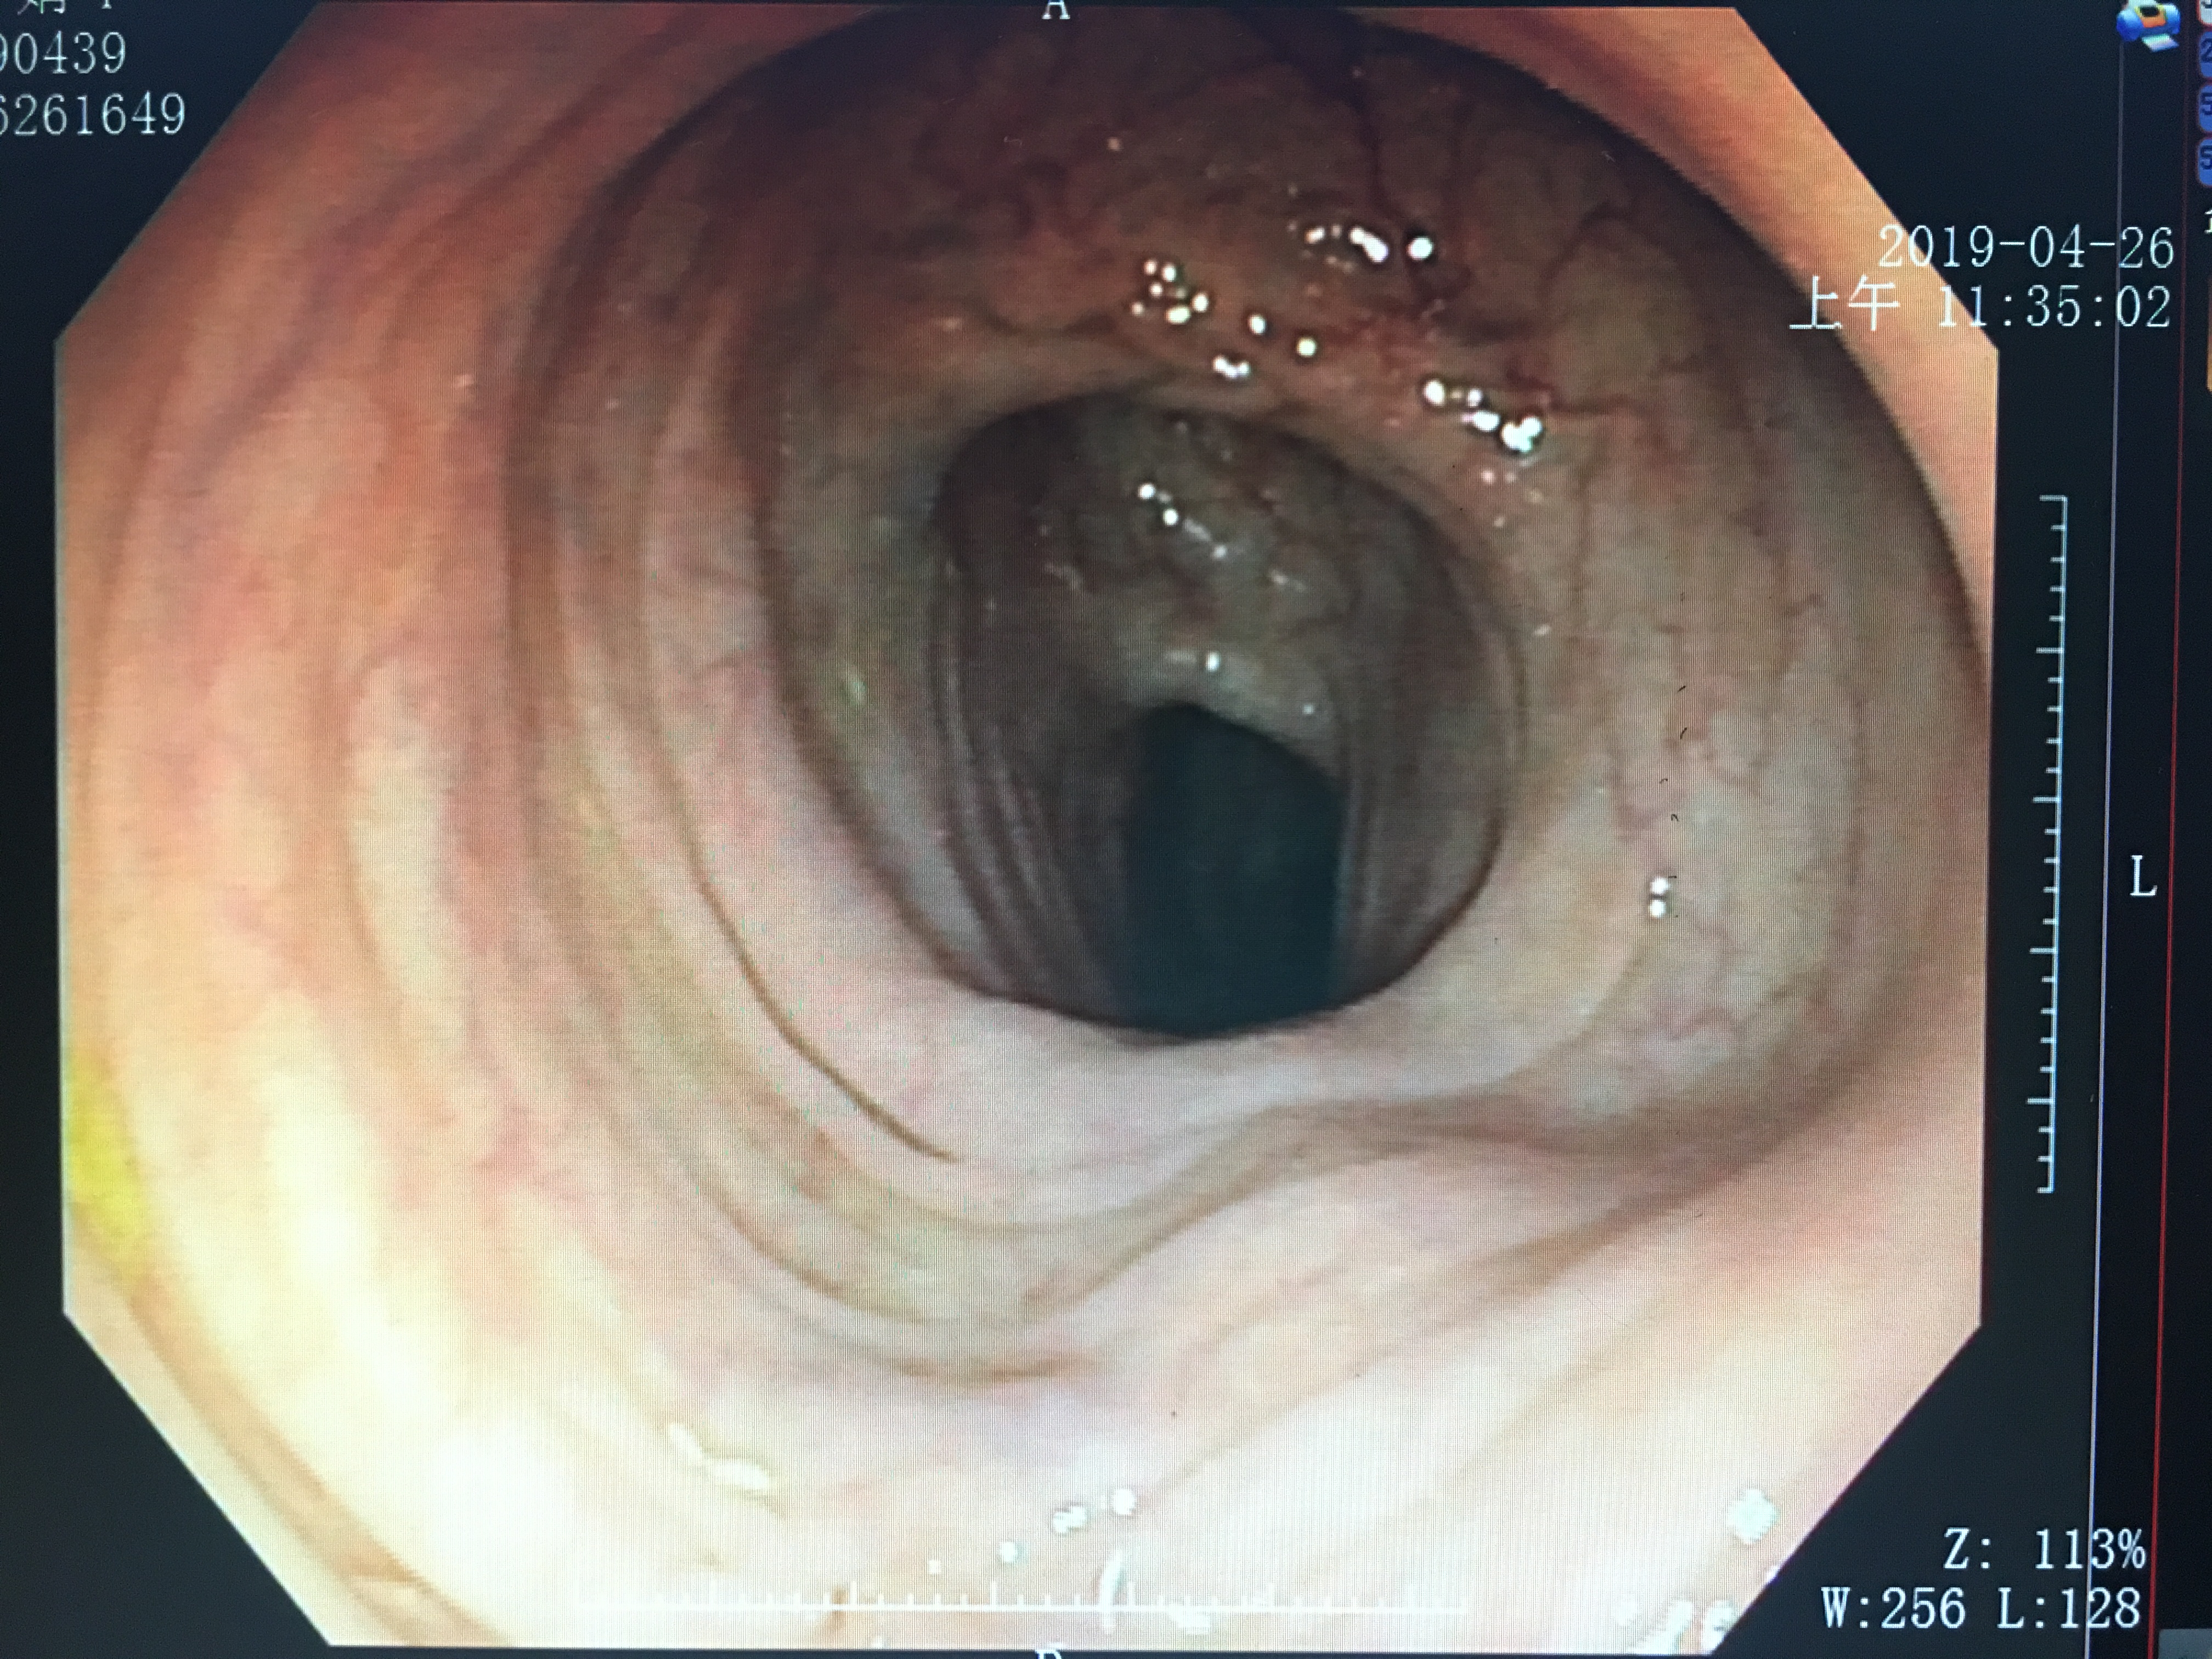

肠道准备的好的镜下

肠道准备欠佳的镜下

通过两张图片的对比,可以明显看出,肠道准备做的好镜下可以清晰看到肠壁的情况,而肠道准备欠佳的则由于食物残渣、粪便等覆盖影响而部分肠壁显示不清,甚至因为肠道准备不充分的缘故,掩盖了病变的部位,而造成漏诊等。